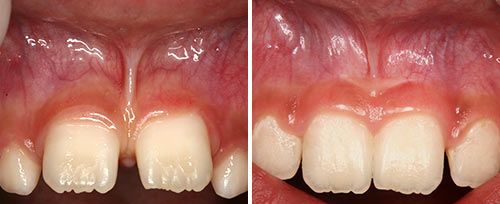

Crown Lengthening

Courtesy of: Boris Gašpirc, DDS, Ph.D.

Laser source: Er:YAG (2940 nm)